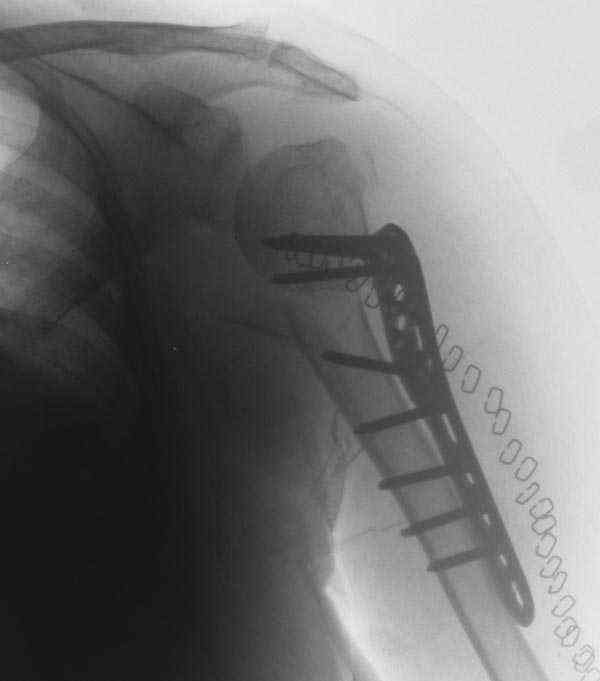

Another option could be closed nailing, see an example, the surgery was done 2 days ago. In common such surgeries are performed under regional anesthesia, not general.

The reduction is not perfect. The patient is very small made, and it was difficult to bring the plate proximally without impingement in abduction.

Pain relief after surgery was early and sustained.

I agree that this reduction is not perfect. The gap may later result with nonunion. Such or even better reduction can be reached without site

opening as you mentioned. Locking plates are positioned as less invasive, why so long incision was - even longer than plate?

Pls compare wound size visible at x-rays of your example with ones after typical closed nailing of the proximal humerus.